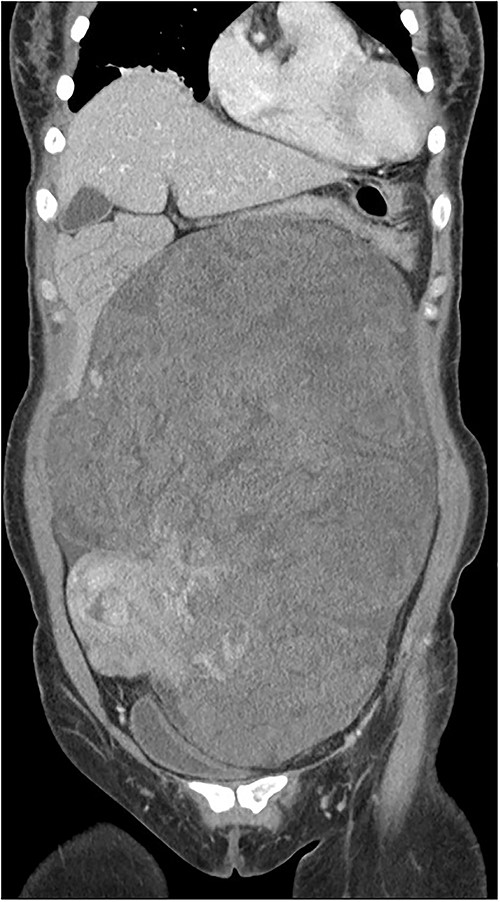

The tumor was wrapped in a grayish-white capsule in a lobulated pattern, accompanied by bleeding; necrosis was not apparent. Yellow dot-like cellular components were observed. The findings for the spindle cell neoplasm (46.5 × 25.0 × 8.0 cm) were a smooth-muscle tumor of uncertain malignant potential (stump), with necrosis absent, a mitotic count <4/10 HPF, and moderate-to-severe and focal nuclear atypia (Fig. 3). Based on these results, the diagnosis revealed that the tumor originated from smooth muscle cells and was classified as a spindle cell tumor. Immunohistological analysis showed negative results for CD34, c-kit, PAN-CK, EMA, and S-100 and positive results for Desmin and SMA. The Ki-67 index was 5% (Fig. 4).

The tumor was composed of spindle cells with moderate to severe, focal nuclear atypia.